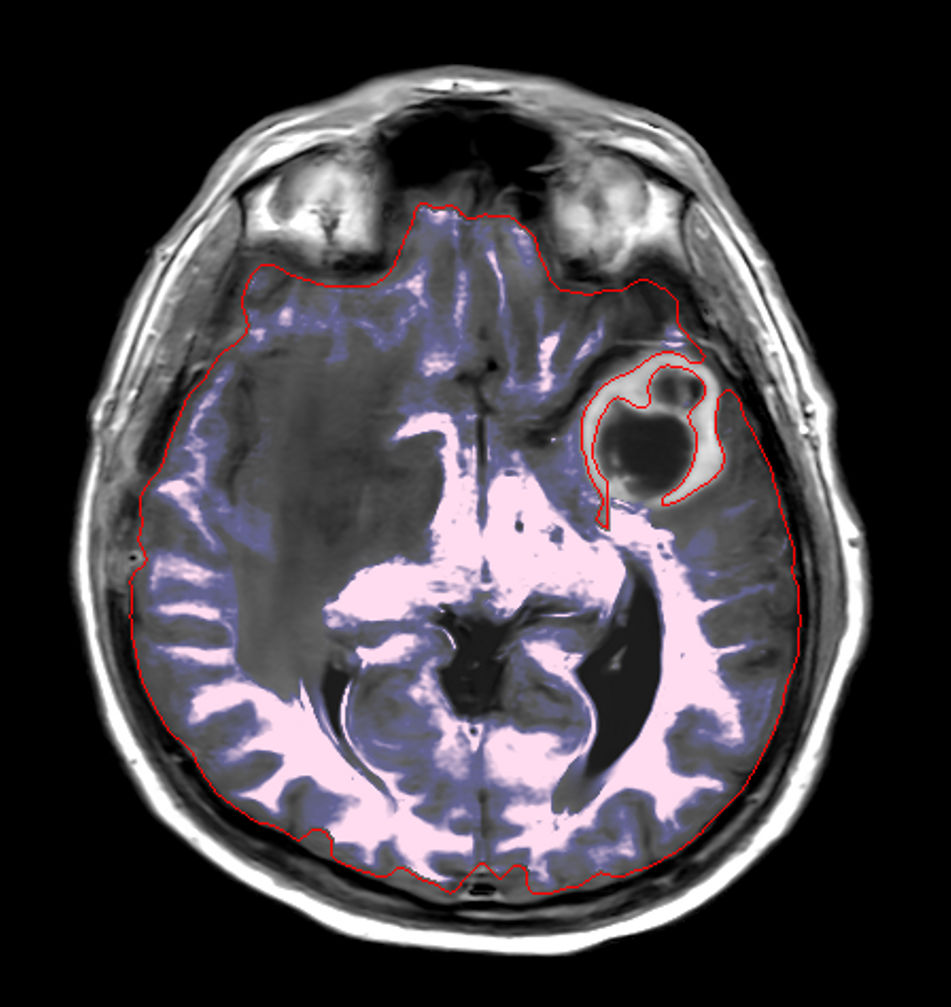

Patient with a large brain lesion. AI based SmartSpeed is utlized to shorten scan time without compromise in image quality. Advanced imaging techniques like pCASL and 3D APT are used to perform contrast-free brain imaging to assess perfusion and tumoral activity. SWIp 3D susceptibility weighted offers the high sensitivity required to visualize deoxygenated (venous) blood or calcium deposits. A single synthetic (SyntAc) brain quantification scan is added. The resulting data of this scan can be used as input for advanced third party processing software* to synthesize MR images with different contrasts, brain parenchyma fraction maps and/or brain segmentation maps.

Axial 3D APT